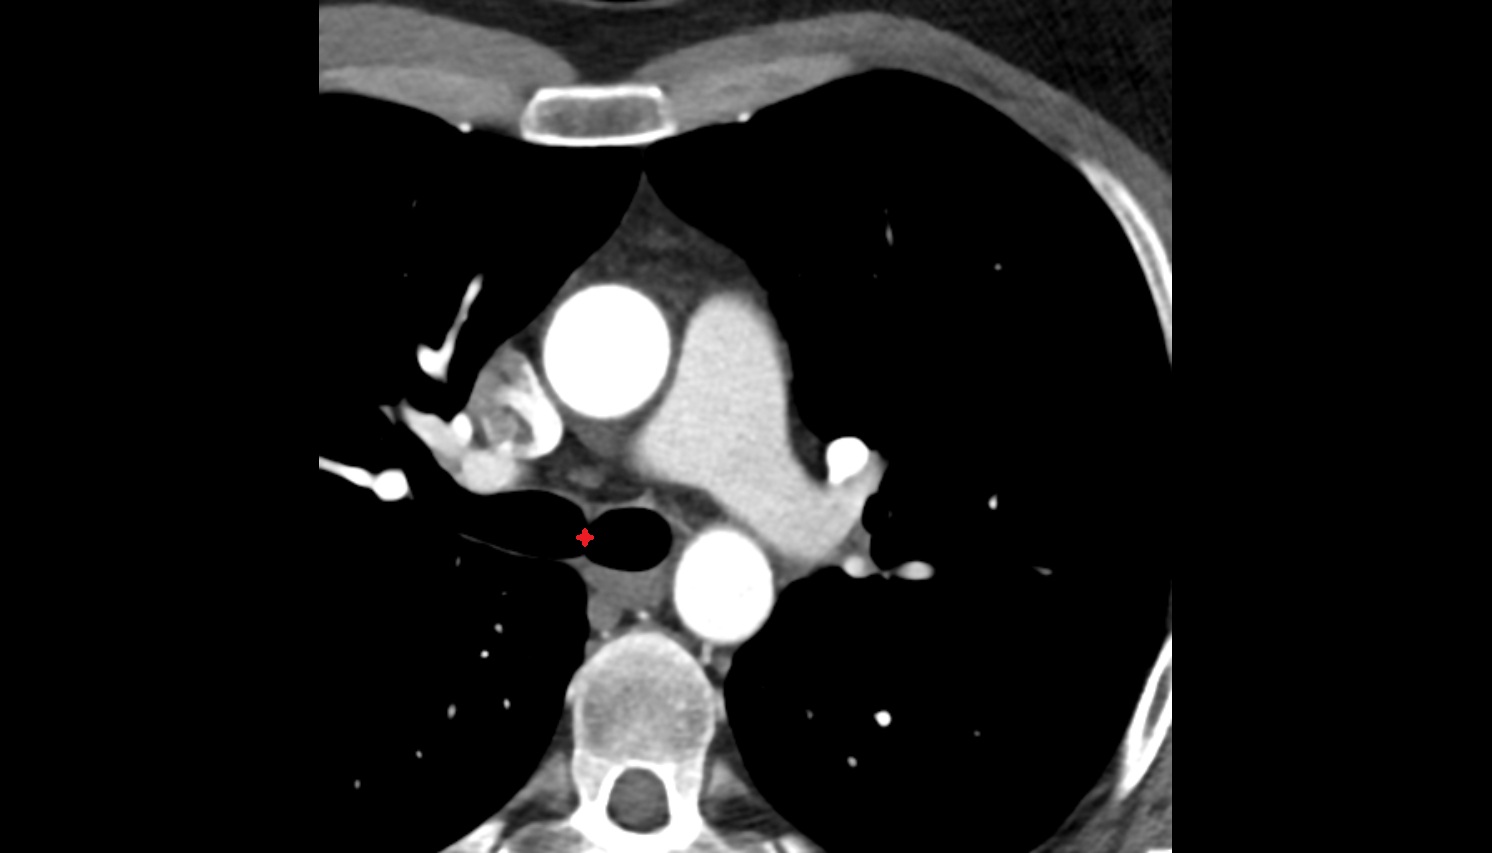

- Pericardium

- Heart

- Left ventricle

- Right atrium

- Left atrium

- Right ventricle

- Pulmonary trunk

- Ascending aorta

- Arch of aorta

- Superior vena cava